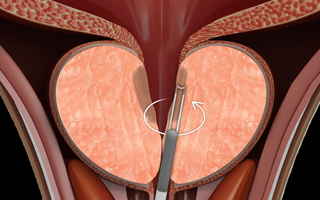

03

3단계

플라즈마 장비를 회전시키며 치료부위를 넓혀줍니다.

-

04

4단계

지혈과 치료부위를 확인하고 치료를 마무리합니다.